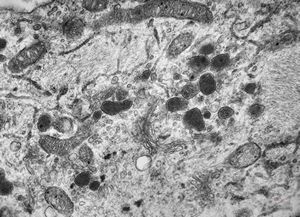

F, 24y. | molluscum contagiosum … virions

F, 24y. | molluscum contagiosum

F, 24y. | molluscum contagiosum